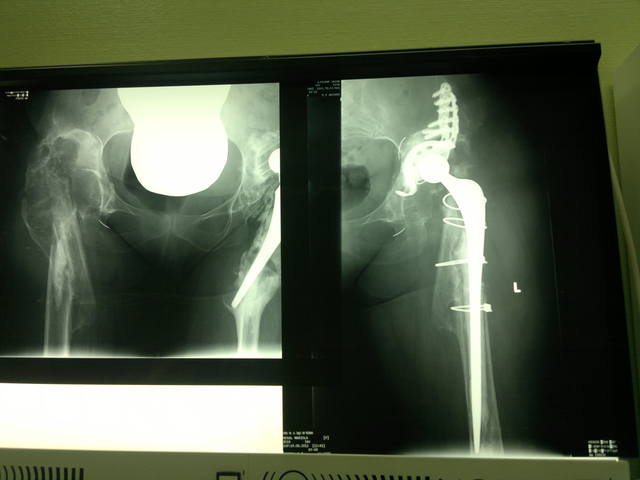

<br /><br />Женщина 54 года, оперирована с обеих сторон около 5 лет назад. Примерно 1 год назад получила перипротезные переломы с обеих сторон. Слева - выполнено ревизионное эндопротезирование. Справа - удален эндопротез, в плане - тотальное ревизионное эндопротезирование.<br /><br />Господа-протезисты, Ваши предложения в этом случае?<br /><br />